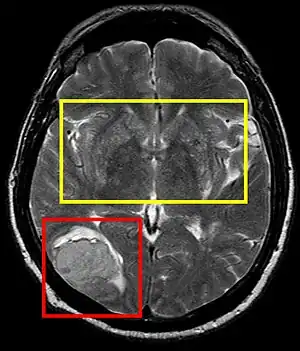

Sistema nervioso central

La hipertensión arterial persistente puede causar un accidente cerebrovascular trombótico o embólico, infartos lacunares o un accidente cerebrovascular hemorrágico con hematoma intracerebral, entre otros. Tanto la presión sistólica y diastólica elevadas son perjudiciales; una presión diastólica de más de 100 mmHg y una presión sistólica de más de 160 mmHg han dado lugar a una incidencia significativa de enfermedades cerebrovasculares. Otras manifestaciones de la hipertensión incluyen la encefalopatía hipertensiva, lesiones microvasculares cerebral y la demencia de origen vascular como consecuencia de múltiples infartos del sistema nervioso central.[13]